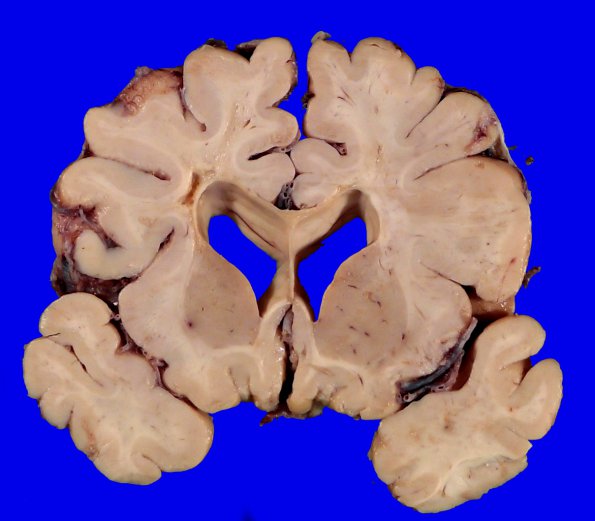

Washington University Experience | MYELIN (NON-IMMUNE MEDIATED) | Retinal Vasculopathy with Cerebral Leukoencephalopathy (RVCL, TREX1 Mutation) | 17B6 RVCL (Case 17) Gross _9

176,7 The cystic lesion in the left periventricular region is accompanied by a more diffuse injury in the adjacent white matter seen better at higher magnification in image 17B7. White matter injury has produced atrophy of the corpus callosum.